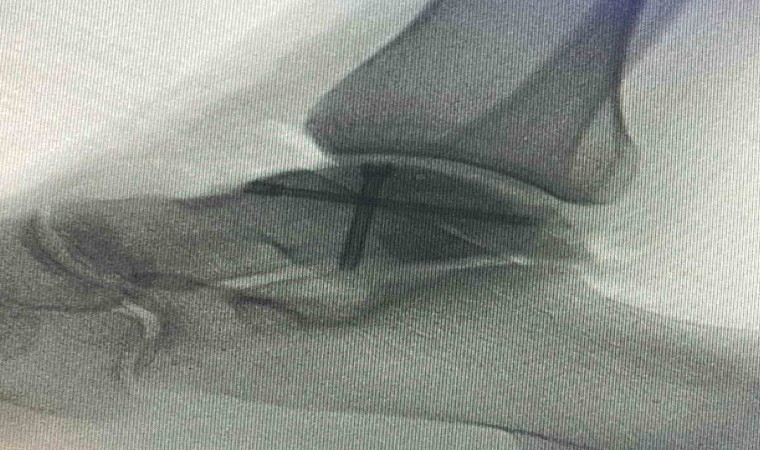

Sağlık alanındaki teknolojik gelişmelerin ve güncel uygulamaların yakından takip edildiği Balıkesir Üniversitesinde gerçekleştirilen ameliyatla ilgili bilgiler veren Ortopedi ve Travmatoloji Anabilim Dalı Öğretim Üyesi Doç. Dr. Aziz Atik; “Lenf kanseri olan 21 yaşındaki hastamız lenf kanseri tedavisi görerek sağlığına kavuşmuş ancak ilerleyen zamanlarda aldığı tedavilerin yan etkisi olarak ayak bileği kemiğinde çürüme meydana gelmiş. Bize başvuran hastamızın eklem yüzeyi bozulmuş ve hastamız yürümekte zorlanıyor, topallıyordu. Büyük bir lezyonu olan hastamıza büyük lezyonlarda uygulanan en iyi tedavi yöntemi olan ve nadir olarak yapılan bir ameliyatla kadavra donörden kemik ve kıkırdak doku nakli gerçekleştirdik.” ifadelini kullandı. Ülkemizde kemik ve kıkırdak bankası olmadığının altını çizen Doç. Dr. Aziz Atik, yurt dışından bir donör bulmak için çalışmalar yaptıklarını ve yurtdışından kemik bulunduğunda ivedi bir şekilde ameliyatı gerçekleştirdiklerini söyledi. Ameliyatın son derece başarılı geçtiğini belirten Doç. Dr. Aziz Atik, güzel bir eklem düzeyi elde ettiklerini ve ameliyatla genç bir insanın topallamadan, ağrısız yürümesini hedeflendiklerini dile getirdi.